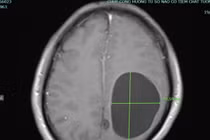

Cả 2 bệnh nhân bị nang sán não do sán dây chó vì thói quen ăn tiết canh. Sán có thể xâm nhập vào gan phổi, lách, thận, tim, xương và não... người dân cần chú ý.

Người bệnh Hà Văn K (60 tuổi), tại huyện Thanh Sơn thường xuyên ăn tiết canh, rau sống… Khi bị đau đầu, liệt nửa người phải nhập viện thì được chẩn đoán mắc đa nang kén sán não.

Có thói quen ăn tiết canh để giải nhiệt và "giải đen", ông L.V.B (68 tuổi, ở Thanh Hóa) thường xuyên đau đầu, co giật, sùi bọt mép, đi khám bất ngờ phát hiện tổ sán chi chít trong não.